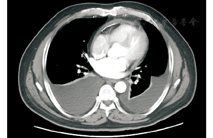

患者男性,47岁,因"腹胀20余天,胸闷、憋气15天"入院。患者入院前20余天无明显诱因出现腹胀,进行性加重,偶伴恶心、呕吐。15 d前出现胸闷、憋气,多于活动后出现,休息后可缓解,同期出现尿量减少、双下肢水肿。7 d前突发憋喘加重,伴大汗,休息后缓解。症状出现后患者饮食差,体重在20 d内增加5 kg,体力明显下降,平地步行200 m即感喘憋。期间予强心、利尿、对症治疗,效果不明显。既往体健。查体:体温36.5℃,脉搏140次/min,呼吸18次/min,血压141/101 mmHg。巩膜轻度黄染,双下肺呼吸音减低,无明显干湿啰音,心律齐,心率140次/min,心音略低,各瓣膜区未闻及明显杂音,腹部膨隆,触诊不满意,叩诊实音,肠鸣音未及,双下肢对称性水肿,达膝上1 cm。实验室检查:白细胞6.6×109/L,血红蛋白121 g/L,血小板258×109/L,总胆红素22.8 μmol/L,直接胆红素10.8 μmol/L,谷草转氨酶32 U/L,谷丙转氨酶22 U/L,肌酐66 μmol/L,血沉7 mm/第1小时,C反应蛋白1.1 mg/dl,转铁蛋白184 mg/dl,补体C3 112 mg/dl,补体C4 21 mg/dl,免疫球蛋白G 1 490 mg/dl,免疫球蛋白M 321 mg/dl,免疫球蛋白A 317 mg/dl,免疫球蛋白G1 10.6 g/L,免疫球蛋白G2 3.85 g/L,免疫球蛋白G3 0.416 g/L,免疫球蛋白G4 0.668 g/L,NT-proBNP 1 137 pg/ml,结核抗体实验(-),PPD试验(-)。心电图提示心房扑动,心室率140次/min,V2~V5导联ST段压低;超声心动图提示左心房扩大,室壁运动普遍减低,左心室射血分数46%,室间隔处二尖瓣环e′值12 cm/s,侧壁处二尖瓣环e′值8.46 cm/s。胸部CT提示心包不均匀增厚伴钙化,双侧胸腔积液,双下肺膨胀不全,两侧胸壁软组织水肿(图1),腹部超声提示肝大,肝中静脉和下腔静脉增宽,符合肝淤血表现,少量腹腔积液。入院后诊断缩窄性心包炎,于全麻下行心包剥脱术。病理提示心包明显增厚,有多量浆细胞、淋巴细胞浸润,有淋巴滤泡形成,纤维组织增生伴玻璃样变性,可见纤维素渗出,免疫组化结果:CD138(浆细胞+),CD38(浆细胞+),IgG1(+),IgG2(+),IgG3(+),IgG4(>20/HPF),CD20(B细胞+),CD3(T细胞+),CD4(T细胞++),特殊染色结果:弹力(+),诊断为IgG4相关性缩窄性心包炎(图2、图3)。术后患者心律转为窦性,症状明显改善,嘱患者出院后继续糖皮质激素治疗,但患者未服用激素治疗。